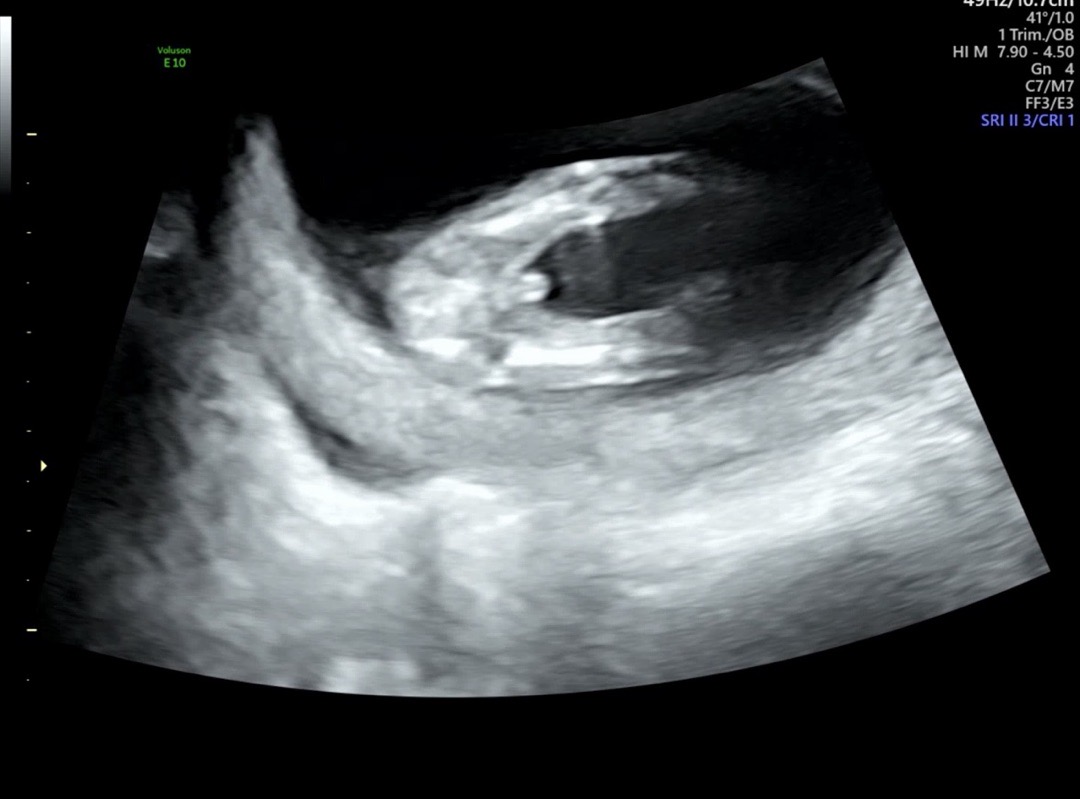

12주4일 니프티+입체하고왔어요 🌶️존재감..!

존재감이 너무 뚜렷하다고 하셔서 아들맘인것같은데! 성별반전이 있을지 니프티 결과 궁금해지네요 😀 다리사이에 보석반지같은게 따악 💎 1차 기형아검사 정상이라 이제 마음편하게 안정기에 진입했습니다🥰